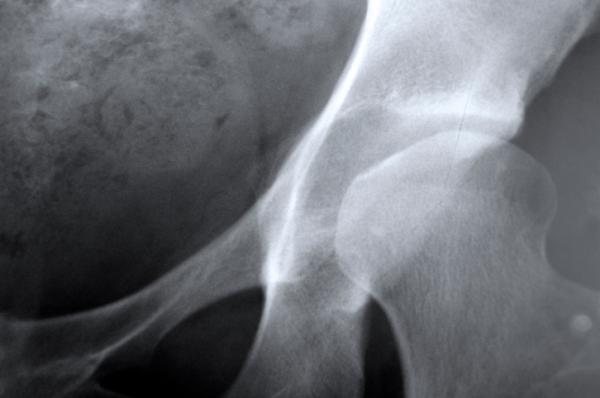

Fra le donne con più di 45 anni, ad esempio, sono più i giorni trascorsi in ospedale a causa di fratture (che rappresentano la conseguenza più drammatica della perdita di densità ossea dovuta all’osteoporosi), rispetto a altre malattie come diabete, infarto, tumore al seno. E l’esperienza riguarda una donna su tre dopo i 50.

La patologia, infatti, è favorita dal brusco calo di estrogeni che si verifica con la menopausa. Va da sè che con l’aumento dell’aspettativa di vita aumenterà la pressione sui sistemi sanitari, anche a causa dell’osteoporosi.

La stessa Iof stima che nel mondo oggi vivano circa 200 milioni di donne affette da osteoporosi. In Europa ci si attende che aumentino del 23% , da 27,5 milioni nel 2010 a 33,9 milioni nel 2025. Donne la cui fragilità si riflette pesantemente sulla società: sono loro, le over 50 che si prendono cura dei familiari anziani o disabili, dei bambini. Se cedono, si spezza un sostegno familaire decisivo.